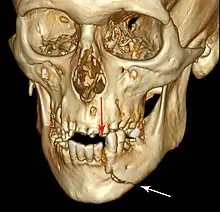

Root fracture

Simple mandible fracture

3D CT of mandible fracture.